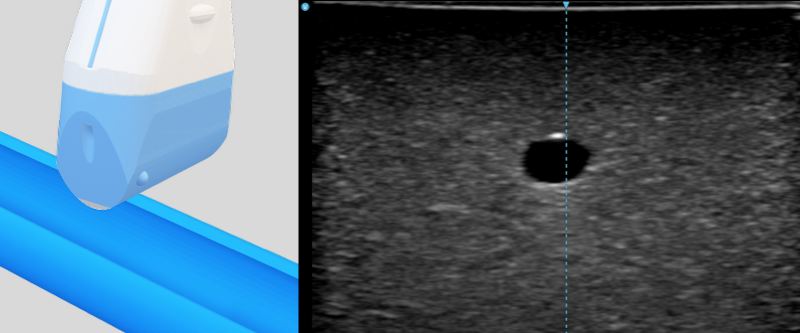

- Short axis (transverse) view: The probe is perpendicular to the travelling direction of the vessel. The vessel appears as a black circle. It is easier for lateral alignment and identification of adjacent structure, but the needle only appears as a dot.

Two compressible veins and one incompressible artery were shown in this clip.